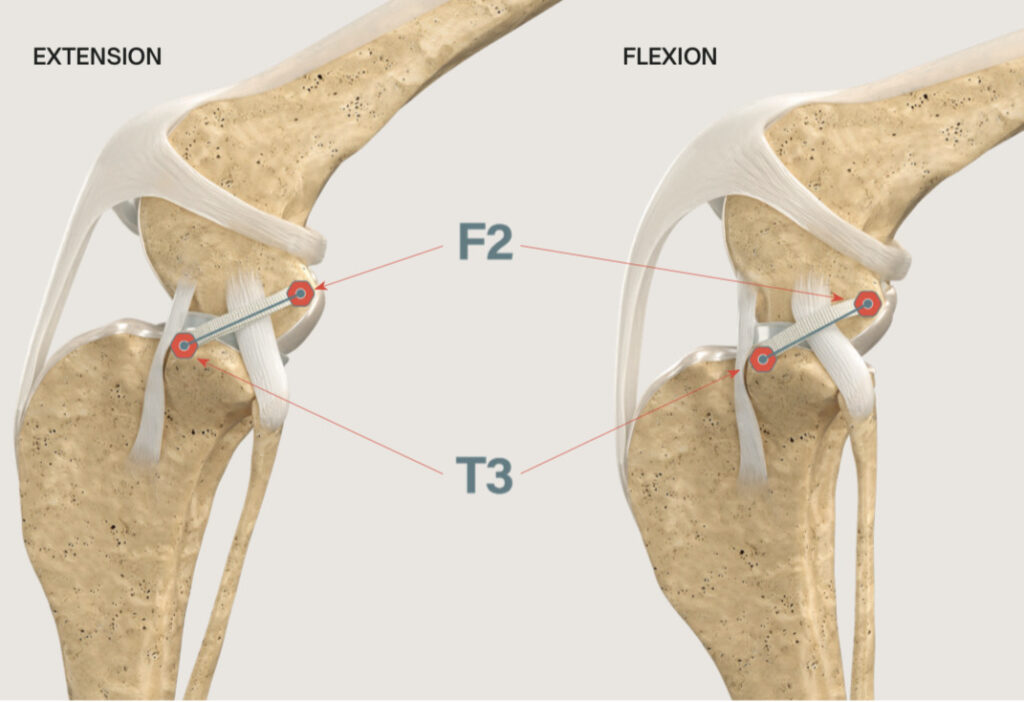

等尺点 F2-T3site

楕円と円の構造の膝関節の中から、等尺点は既に見つかっていました。F2-T3siteと呼ばれる、大腿骨の特定部位(F2)と脛骨の特定部位(T3)の2点を結んだ線は、膝を曲げ伸ばししてもほとんど距離が変わらないことがわかっています。残る課題は、その2点へのアプローチ法と、十分な強度を持つ人工繊維、F2-T3siteに正確に人工繊維を設置する方法でした。これらの課題をクリアできたら、繊維の強度不足による破綻や、たわみから生じる不安定性の残存などの、従来のECRの問題点が理論的には解消されます。